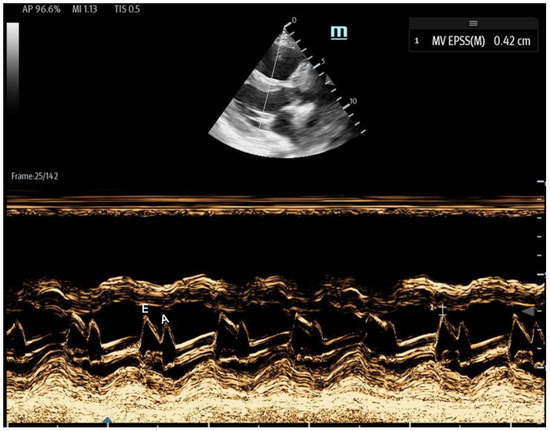

- 1E-point Septal Separation (EPSS): Obtained in the parasternal long-axis (PLAX) view, EPSS quantifies the distance between the anterior mitral valve leaflet tip and the interventricular septum (Figure 11). An EPSS greater than 1 cm may indicate a reduced LVEF of less than 40%, with a sensitivity of 69% and specificity of 91% [54]. This method requires only brief bedside training [55]. However, EPSS may not accurately reflect cardiac function in certain patients. In those with valvular pathologies (e.g., mitral stenosis/prosthesis or aortic regurgitation), abnormal valve or leaflet movement can lead to falsely high EPSS measurements despite normal LVEF. Septal hypertrophy may also underestimate EPSS. Lastly, in atrial fibrillation, the lack of coordinated atrial contractions necessitates multiple measurements for reliable assessments [56].

Figure 11. The parasternal long-axis view with the M-mode shows the EPSS measurement, which is the minimal distance between the E wave (initial and maximal opening of the mitral for the passive filling of LV) and the septum. The E wave is followed by the A wave, which is smaller and corresponds to left atrial contraction. - Fractional Shortening (FS): Obtained in the PLAX view, FS measures the left ventricular (LV) end-systolic and end-diastolic diameters. It evaluates the percentage change in LV diameter between diastole and systole, which is calculated as:FS serves as an estimate of how effectively the LV contracts and can be used as a surrogate for LVEF. However, it may be falsely low in areas of wall motion abnormalities and is highly influenced by preload and afterload. Additionally, FS has been shown to underestimate LVEF in patients with concentric left ventricular hypertrophy [57,58].

- Mitral inflow: Assessed via pulsed-wave (PW) Doppler at the mitral valve tips in the apical four-chamber view, this measures the blood flow velocities entering the left ventricle as an upward deflection of the PW Doppler signal. The resultant E and A waves are then evaluated for their ratio (Figure 14).

Figure 14. Mitral inflow with PW Doppler gate at mitral valve tip (E and A waves). - Tissue Doppler: Measures myocardial movement during diastole using tissue Doppler at the septal annulus. The E/e′ ratio is calculated from the recorded e′ wave (Figure 15).